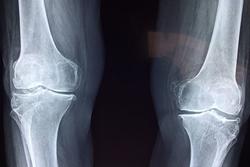

Veniamo ora alla sua domanda. Il dolore articolare è in effetti uno dei principali sintomi della menopausa. E’ causato da un’infiammazione delle articolazioni, che si sviluppa proprio per la scomparsa progressiva degli estrogeni dopo l’esurimento ovarico che segna la conclusione dell’età fertile. La fase infiammatoria, se curata bene e tempestivamente, è reversibile; se invece non si fa nulla, e compare la fase degenerativa, la vera e propria artrosi, l’articolazione subisce lesioni progressive e non più reversibili.

Ciò premesso, tenga presente che il 25% delle donne in menopausa ha dolori particolarmente invalidanti e va incontro a una più rapida deformazione articolare a causa di una mutazione genetica del recettore per gli estrogeni. Se i dolori che lei ha sono particolarmente intensi, varrebbe la pena indagare in questa direzione.